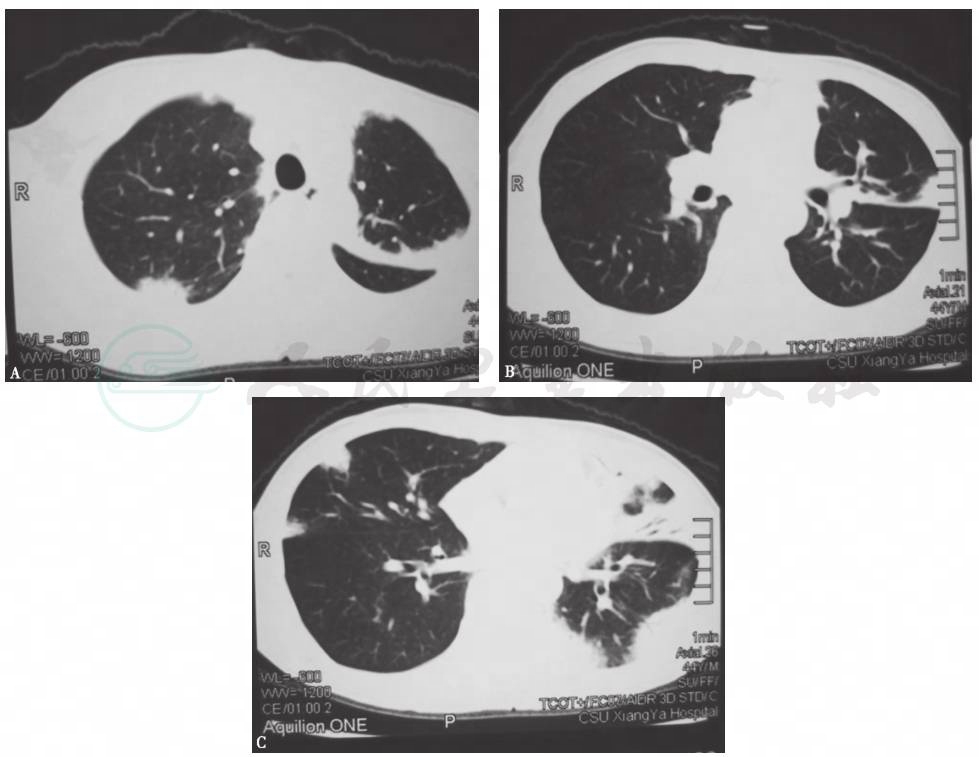

2013年1月4日查胸部CT,见双肺多发实变影,其间可见支气管充气征,伴左侧少量胸腔积液 (图1)。

图1 胸部CT表现(2013-01-04)

患者入院进行抗感染治疗(阿莫西林克拉维酸、亚胺培南西司他汀)10天后,复查胸部CT(2013年1月14日),提示双肺原有实变病灶较前(2013年1月4日)略有进展(图2)。

图2 入院治疗10天后复查胸部CT表现